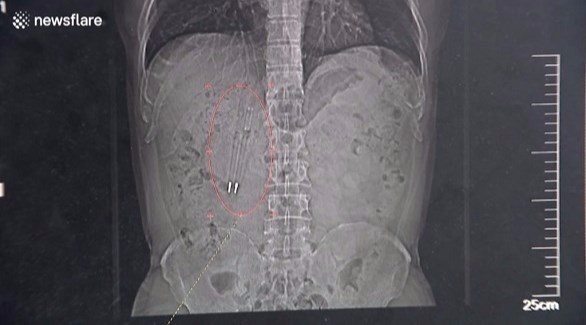

نسي وانج ابتلاعه للأقلام طوال تلك الفترة حتى عندما أجرى صورًا شعاعية لجسمه في فبراير الماضي، وتمكن الأطباء من استخراج الأقلام من معدته في شهر أبريل الماضي، وهو يتمتع بصحة جيدة.